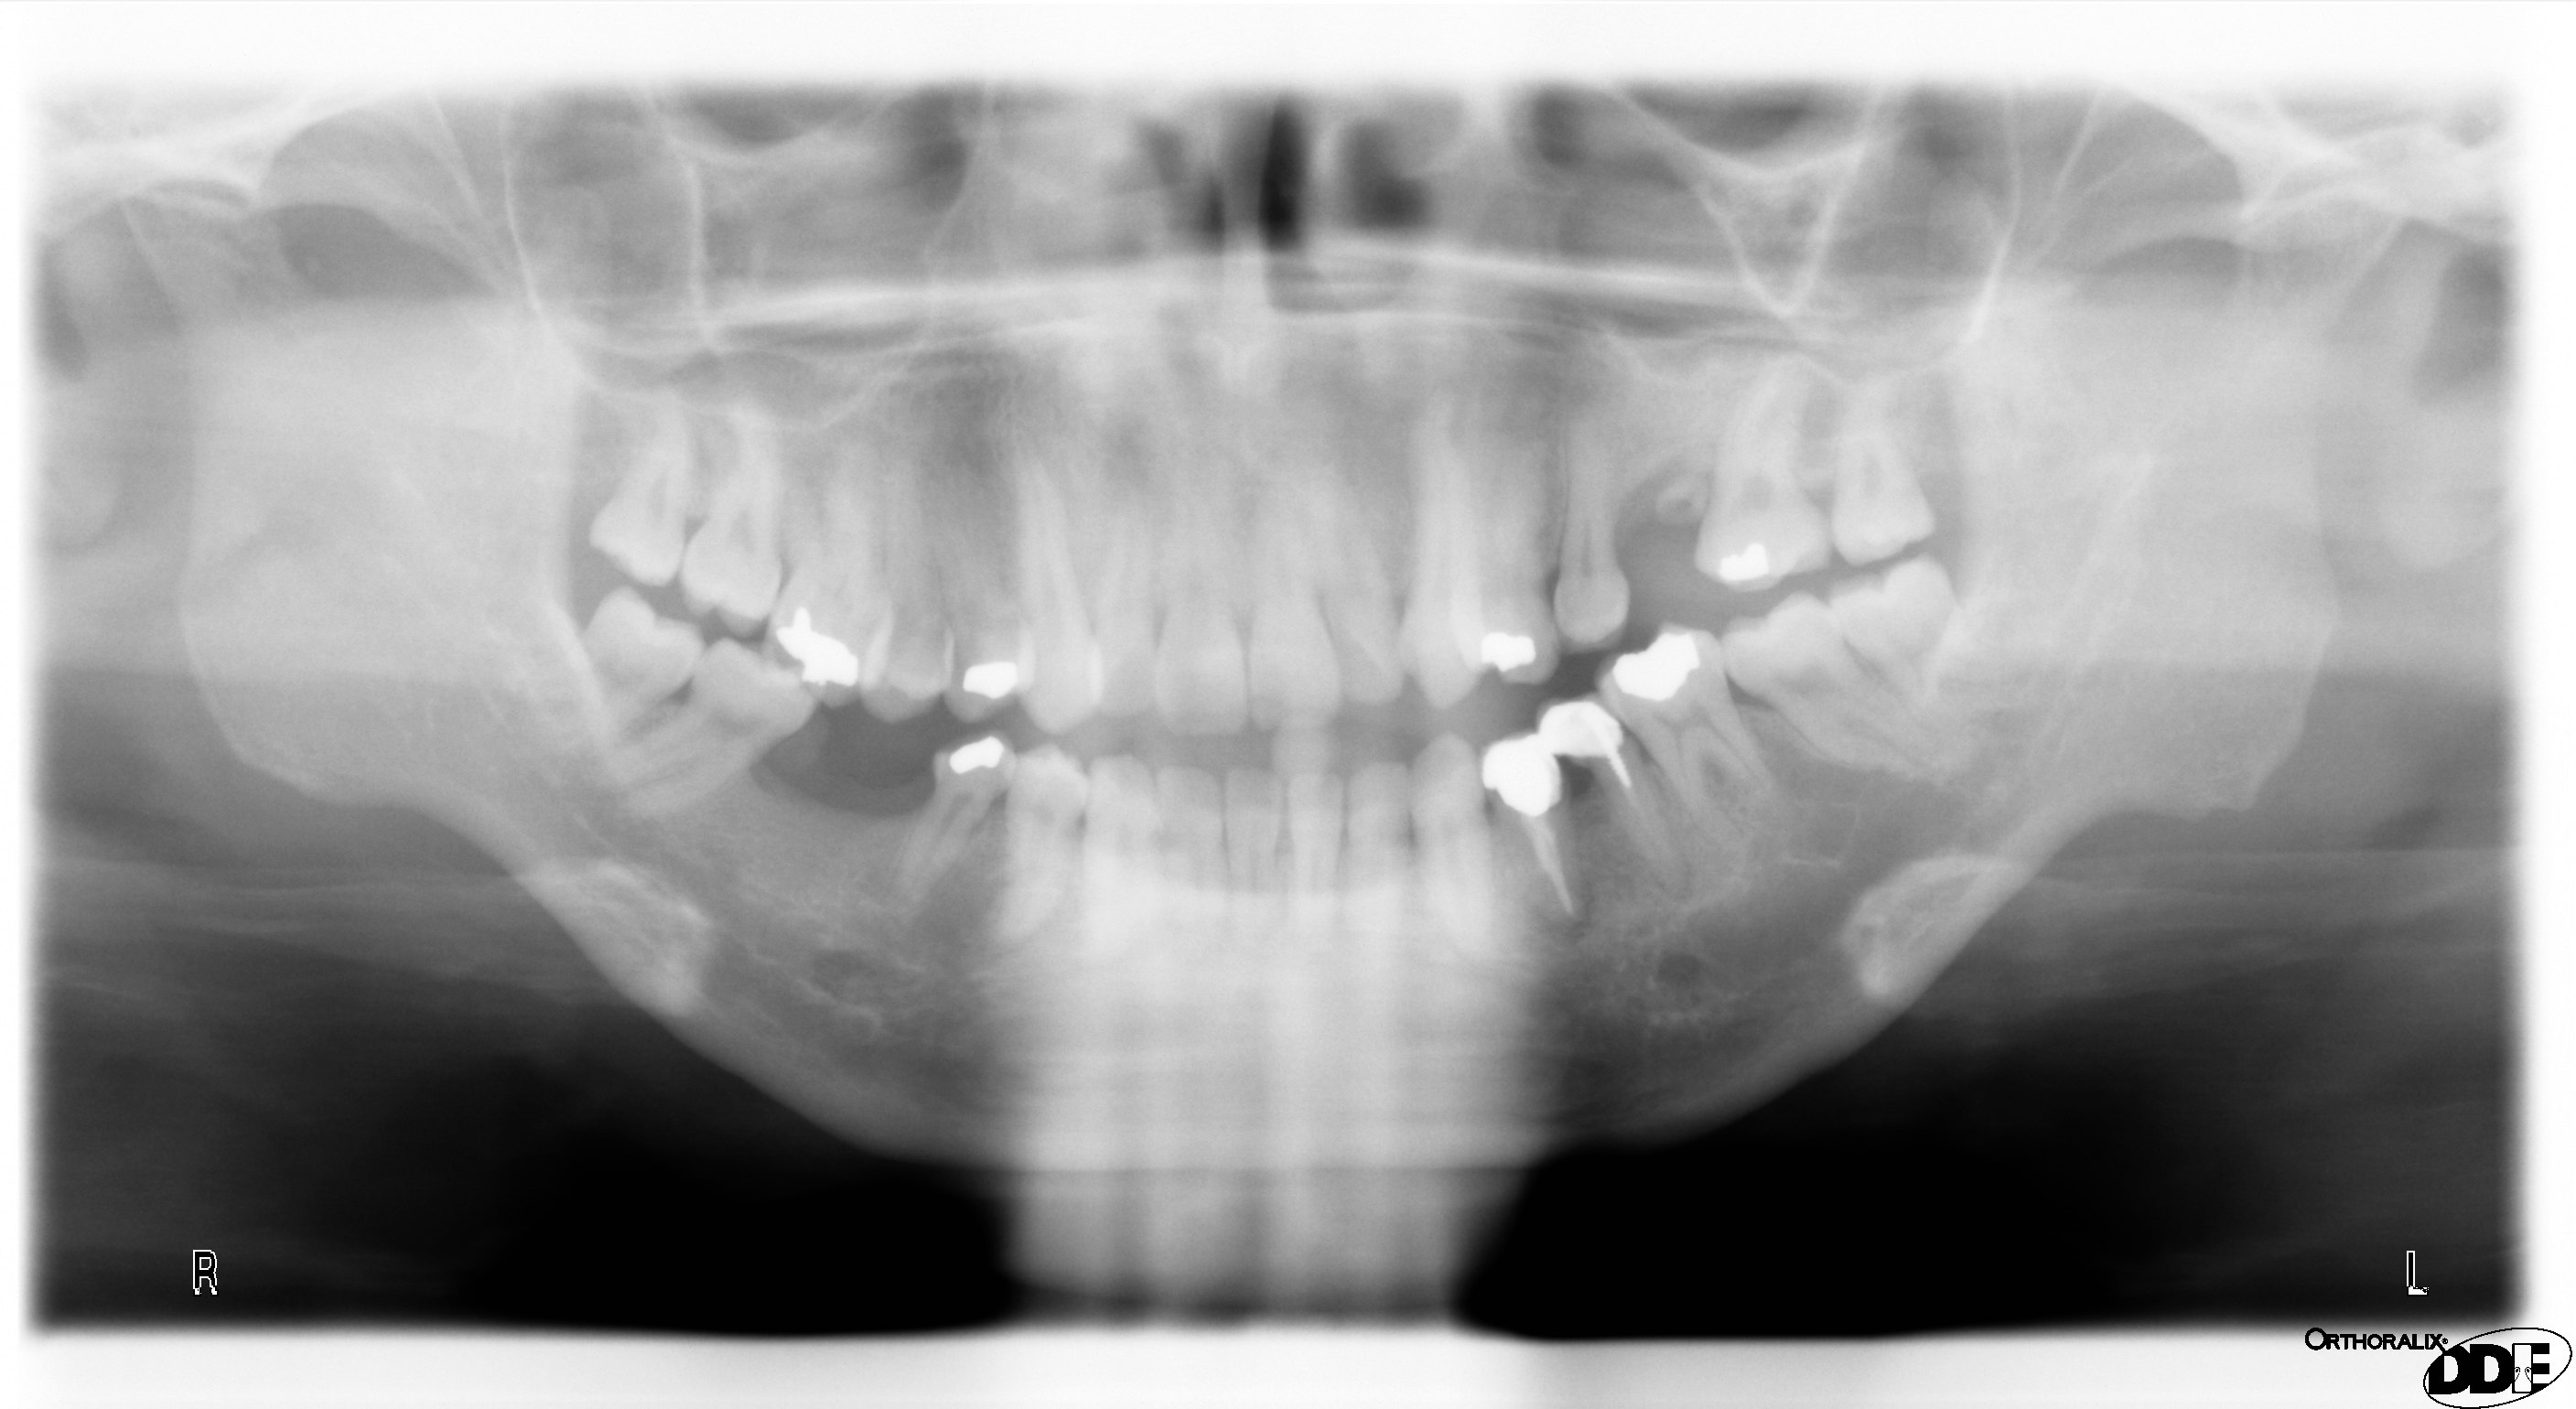

Possibile una tale divergenza?

23-05-2012